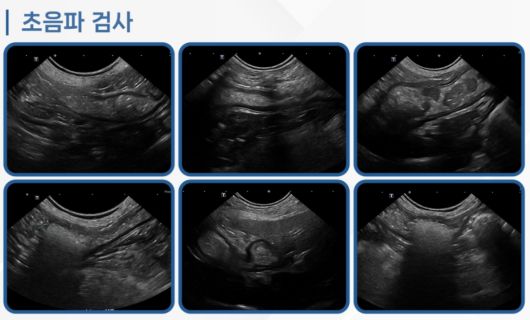

방사선 및 복부 초음파 검사 결과, 위와 소장에 이물이 동시에 과다하게 존재하고 있었다. 이미 장폐색이 진행 중인 상태였다.

코코는 초음파 검사 결과 장폐색이 진행 중인 상태였다(로얄동물메디컬센터 제공). ⓒ 뉴스1 |

특히 공장(소장 중간 부위)에 이물이 걸려 있었다. 이물 앞쪽으로 소장이 확장되며 음식물이 저류된 소견이 확인됐다. 위 내부에서도 다량의 이물이 관찰됐고 담낭 슬러지(찌꺼기)도 동반돼 있었다.